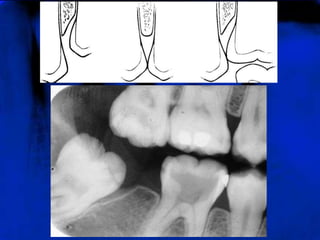

CRISTA ÓSSEAALVEOLAR (RO)

A crista alveolar apresenta-se como uma linha radiopaca

contínua, delgada e lisa, cobrindo, sem solução de

continuidade, o osso esponjoso contido nas cristas e

passando de um dente ao outro, sem interrupção.

CRISTA ÓSSEAALVEOLAR (RO) Acrista alveolar apresenta-se como uma linha radiopaca contínua, delgada e lisa, cobrindo, sem solução de continuidade, o osso esponjoso contido nas cristas e passando de um dente ao outro, sem interrupção.